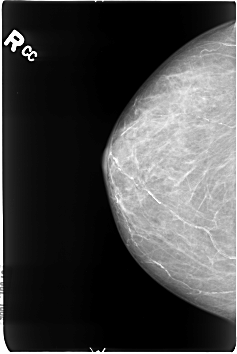

Digital Database for Screening Mammography

Volume: cancer_01 Case: B-3041-1

B_3041_1.RIGHT_CC

filename B-3041-1

DATE_OF_STUDY 26 1 1996

PATIENT_AGE 75

DENSITY 3

RIGHT_CC LINES 4592 PIXELS_PER_LINE 3080 BITS_PER_PIXEL 12 RESOLUTION 50 NON_OVERLAY